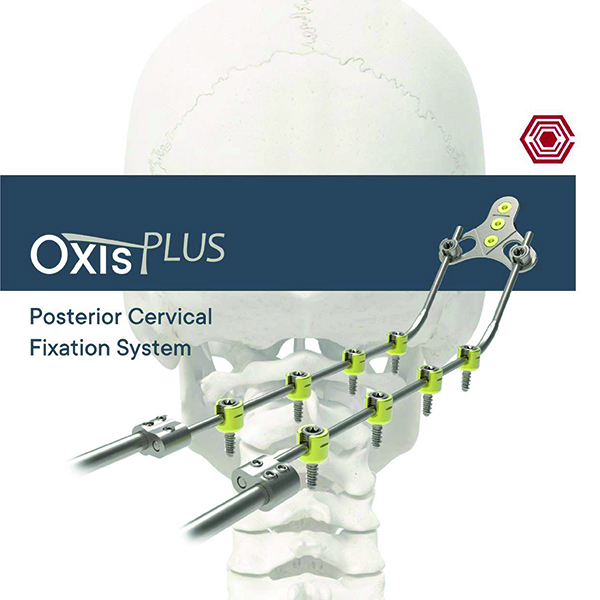

Oxis Plus

Akif Kaya Aybek

Norm Akademi

- Surgical Technique

- Implant Types

- Intrument Container

- Intrument Types

- Oxis Cerrahi Teknikler

- Oxis Plus Cerrahi Teknikler